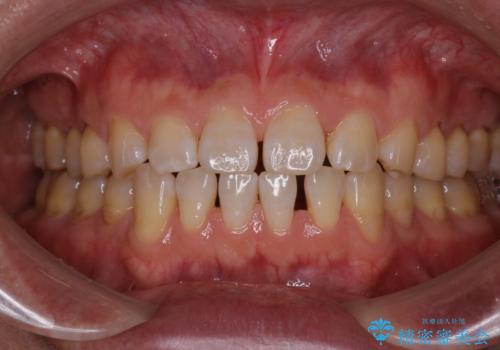

[マウスピース矯正] がたがたの歯並びをきれいにしたい

![[マウスピース矯正] がたがたの歯並びをきれいにしたいの症例 治療前](https://seimitsushinbi.jp/wp/wp-content/uploads/2025/06/0d238550c8a0fddc4de7b2c337c6c786-500x350.jpg?v=1750323380)